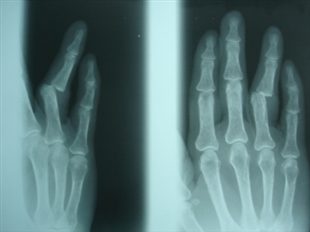

Illustration ici avec une luxation d'un doigt.

« J'ai une luxation d'un doigt, une brûlure à une main et des points de suture à une arcade sourcilière », a-t-il détaillé. Le maire se trouvait avec deux de ses adjoints lorsqu'il a été agressé. Le fait d'annoncer sa qualité d'élu n'a rien changé.